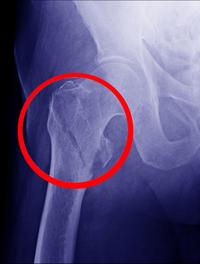

Une première fracture ostéoporotique augmente la probabilité d’une nouvelle fracture, notamment dans les deux années qui suivent l’évènement [...]